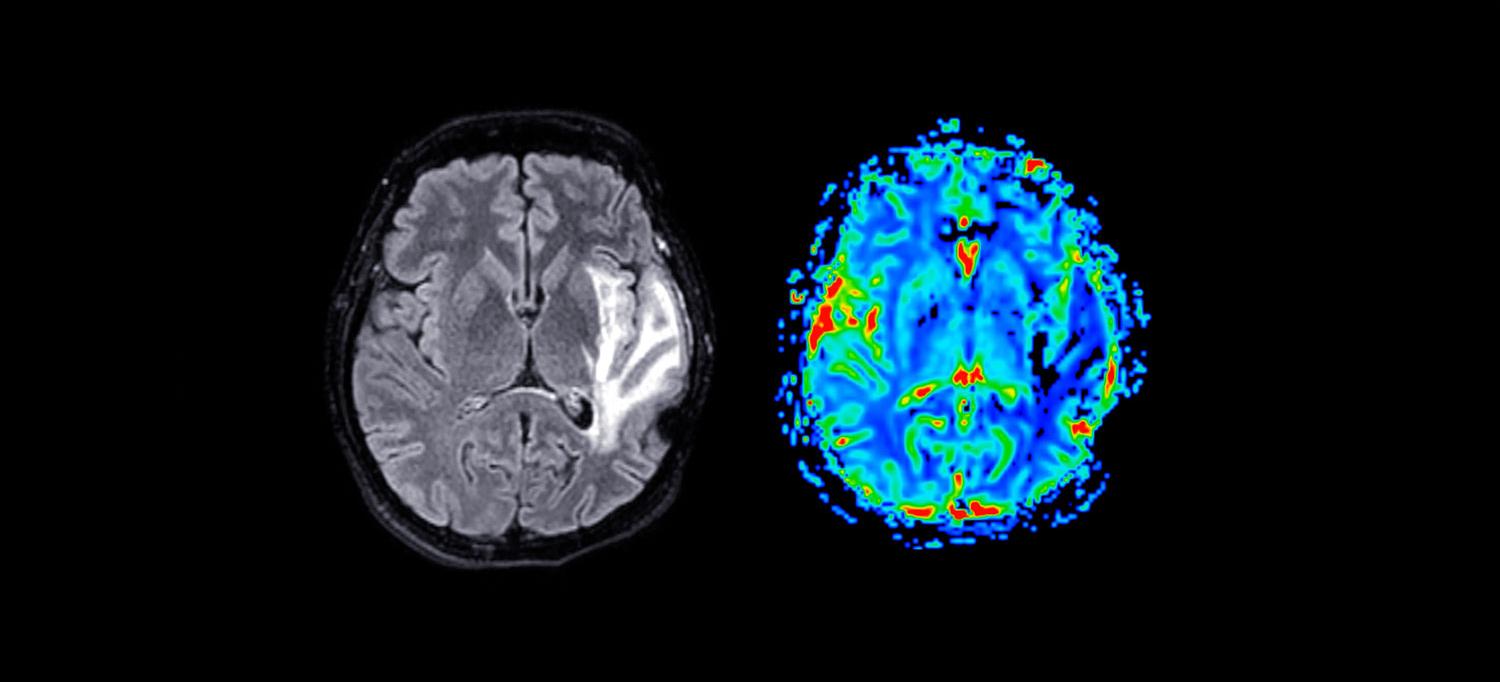

Brain scans from American football players reveal subtle differences in the brain’s outer grooves when compared to scans from otherwise healthy men who never played contact or collision sports, a new study shows. Its authors say the findings could potentially predict which people are more at risk of chronic traumatic encephalopathy (CTE).

Led by an international team of researchers and NYU Langone Health, the study is part of a long-term effort to develop tests for early detection of CTE. Researchers found that football players had shallower left superior frontal sulci on average than their nonfootball counterparts. Left superior frontal sulci are located on a main groove that runs along the top, front, left side of the brain, which is known from past studies to be physiologically affected in CTE. Researchers say sulci are very small and no more than 1.5 millimeters wide and 15 millimeters deep.

Published online in the journal Brain Communications September 11, the study also showed that football players with increasing years of playing experience had wider left occipitotemporal sulci—a groove that runs along the left side of the brain—than men not involved in contact sports.

The study included an analysis of single MRI brain scans from 169 former college and professional football players. These scans were compared to those from 54 carefully matched males of similar age, weight, and education who did not play football or similar sports and who did not have active military backgrounds.